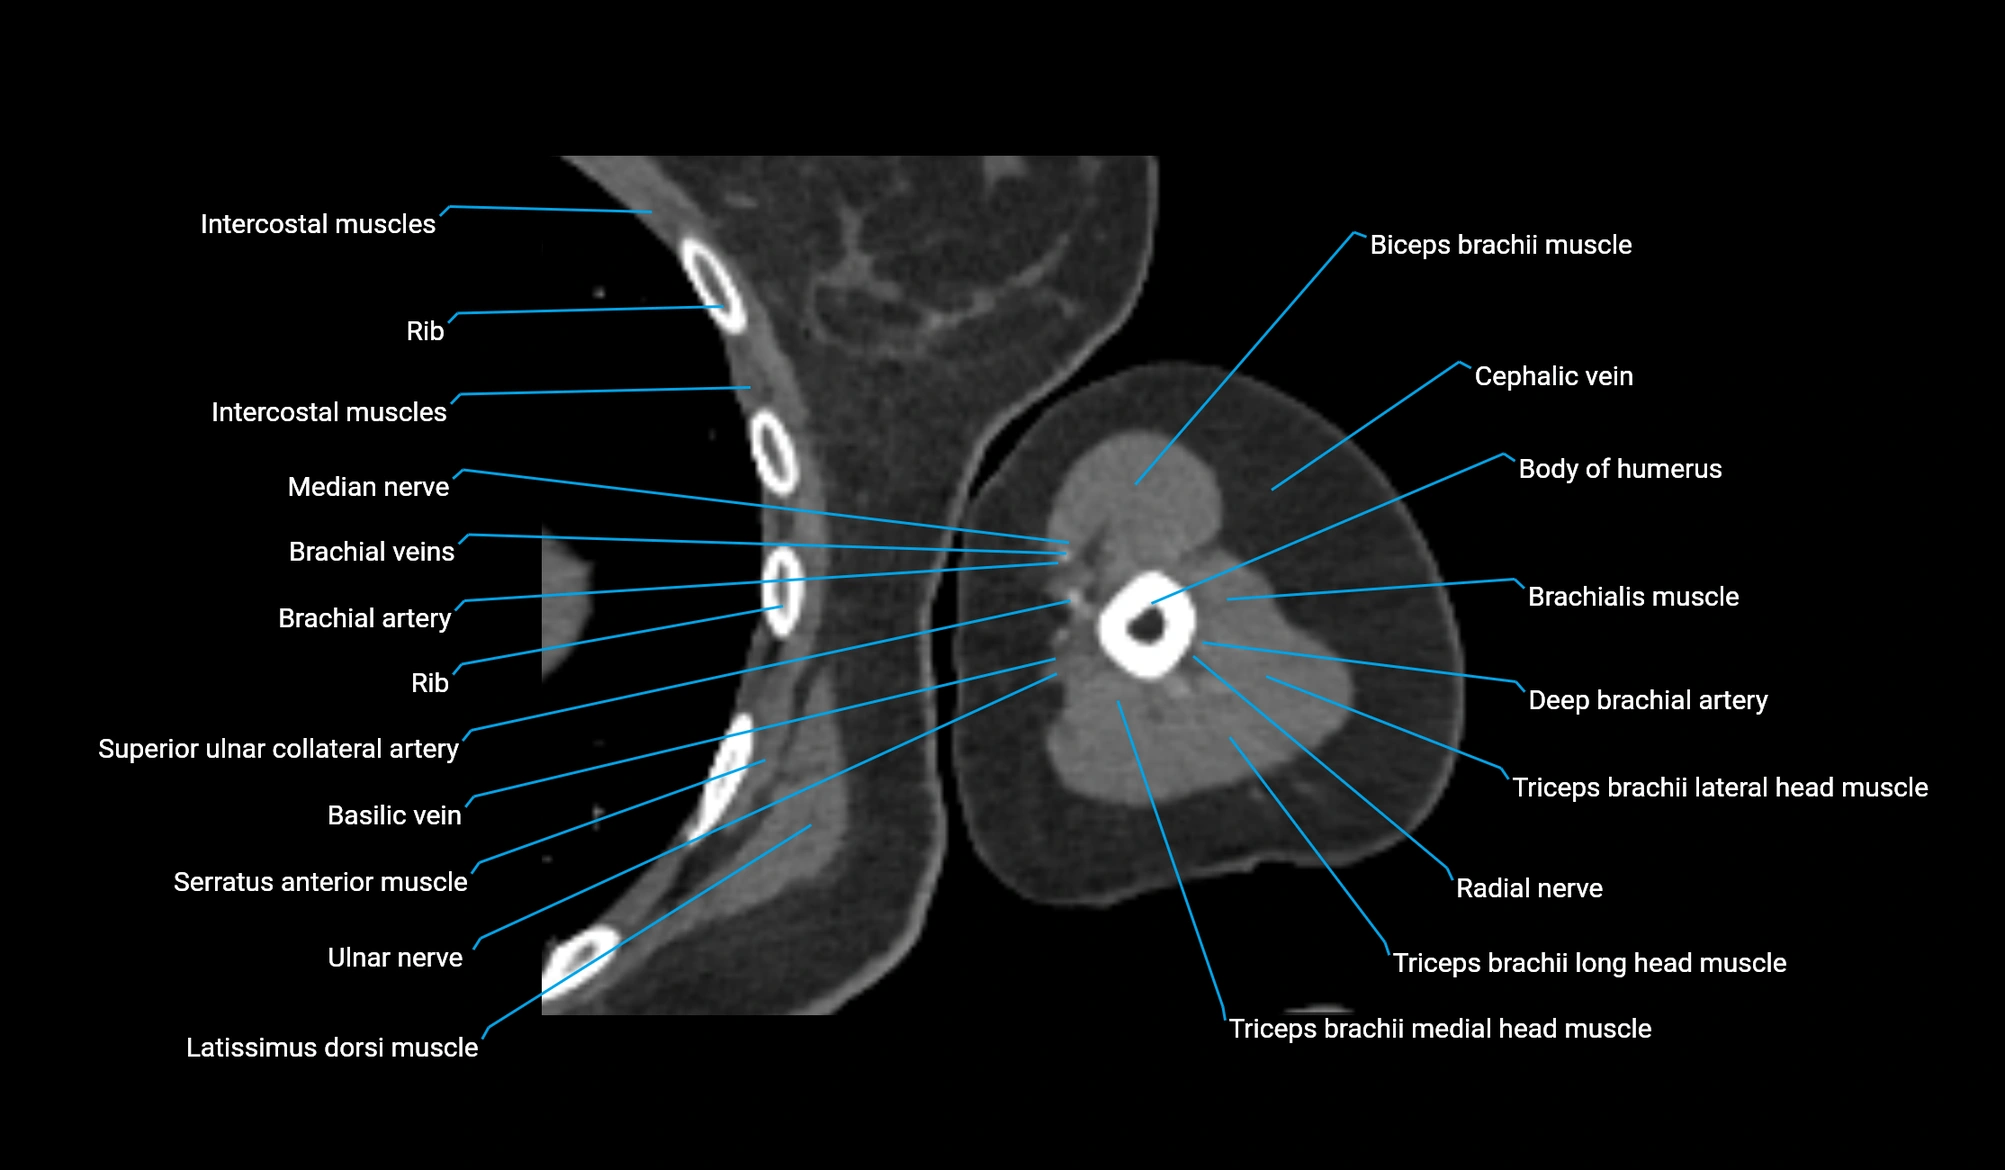

CT image